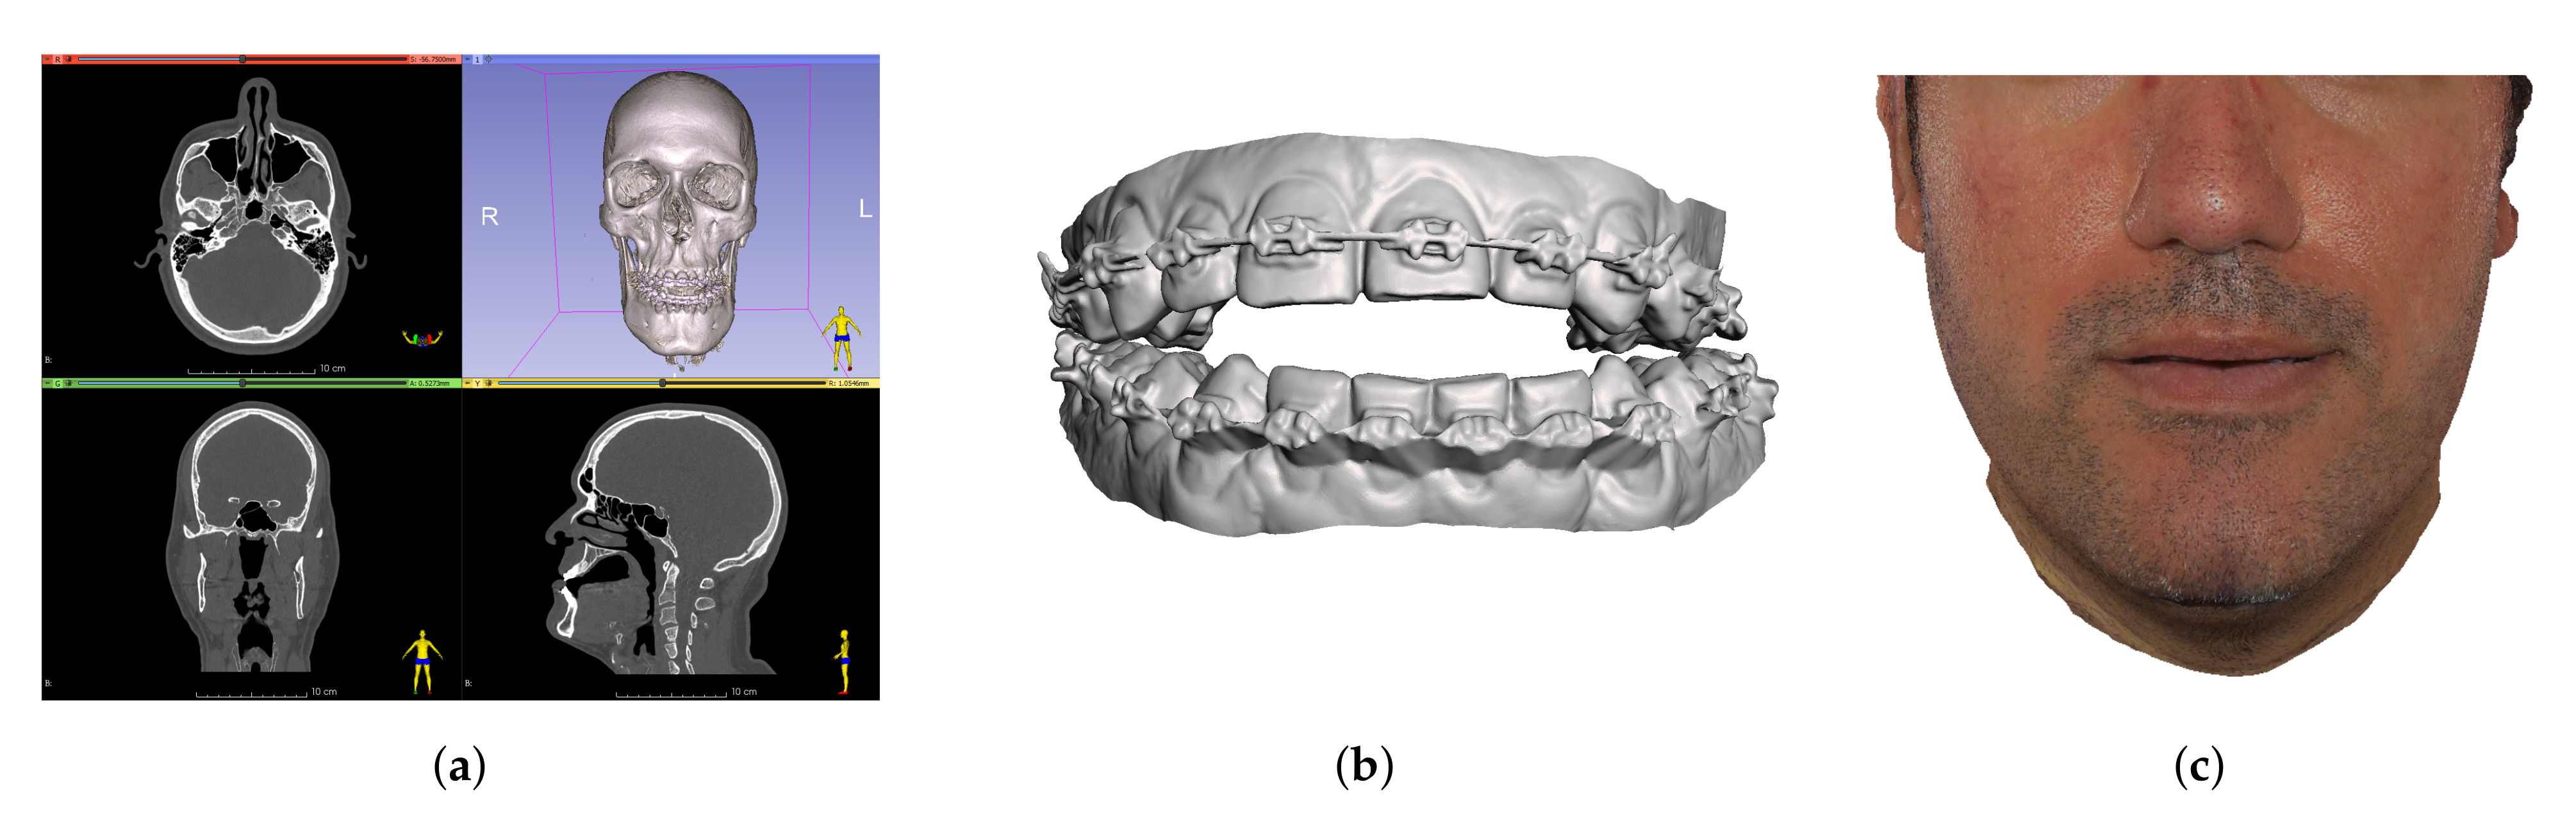

2.5. Preparation of Simulation Meshes and Couplings

2.5.1. Bones

2.5.2. Soft Tissue

2.6. Textured Output Visualization